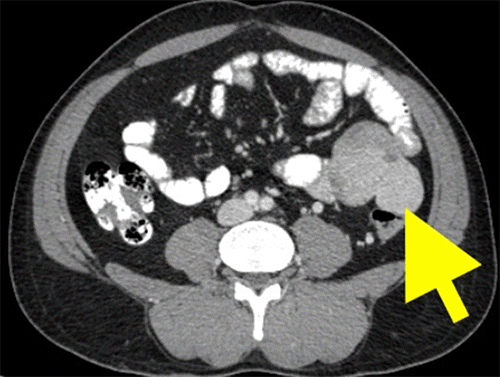

An abdominopelvic contrast-enhanced computed tomography scan showed a soft tissue attenuating mass lesion measuring about 72 × 70 × 60 mm in the left lumbar region extending into the left iliac fossa (Figure 1). There was a heterogeneous gradual enhancement in the tumor with a few foci of necrotic areas. Multiple enhancing venous channels were seen in the vicinity of the lesion, particularly in the posterior and left lateral aspects; it was encasing the adjacent descending colon, causing compression of its lumen. It appeared consistent from the adjacent psoas muscle. The kidney was separate. There was no evidence of metastasis.

Figure 1. CECT of Abdomen. Published with Permission

Scan demonstrates a soft tissue mass lesion located in the left lumbar region, with infiltration into the descending colon